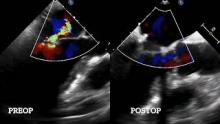

In October 2020, the patient suffered a new non-ST segment elevation myocardial infarction requiring the implant of another stent in the circumflex artery. The echocardiography showed severe mitral regurgitation with ejection fraction (EF) of 35%, and a Mitraclip® was implanted. After a first clip was implanted, the regurgitation was still moderate to severe. Nevertheless, a second clip was not placed because the mean gradient rose to 5mmHg.

Eight months after the procedure, the patient was admitted with worsening heart failure symptoms, and the echocardiography revealed progression of the mitral stenosis gradient (mean gradient 10mmHg) with severe mitral regurgitation. Thereafter, the patient was scheduled for robotically assisted mitral valve surgery.

After coming off bypass, a transesophageal echocardiography showed postoperative results with mild mitral central regurgitation and no significant valve stenosis (mean gradient 5mmHg, maximum gradient 8mmHg). The patient was discharged uneventfully four days after surgery.

Seven months after surgery, the patient was doing well. The echocardiography showed an effective mitral valve repair without mitral regurgitation or stenosis (gradients were stable, EF 50%).